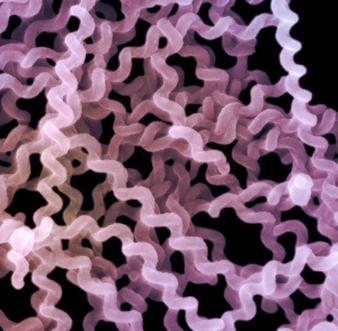

Leptospirosis egy fertőző betegség által okozott Leptospira - mikroorganizmusok élő egész feltételek a magas hő és a túlzott nedvességet. Leptospirosis a leggyakoribb élők a trópusi országokban. Vektor kontroll bevihető :. Kutyák, cickányok, disznók, patkányok, szarvasmarha stb Egy személy megbetegedett leptospirosis, semmilyen veszélyt nem jelent a többi embert.

A diagnózis felállításához magatartási bakteriológiai vizsgálat. Mint már említettük, tudja azonosítani a leptospira A gerincvelői folyadék vagy vér. Ha a betegség vezetjük fázisban toxémia belső szerveket, mikroorganizmusok találtak a vizeletben. Néha az orvos nem tudja azonnal felismeri, és kezdjük a gyanús leptospirosis beteg hepatitis, meningitis, vesegyulladás és más betegségek.